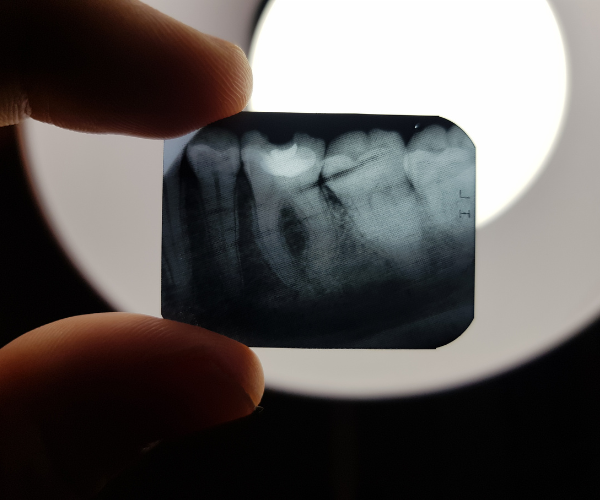

Panoramic dental x-rays are an essential tool in modern dentistry. They provide a comprehensive and detailed view of the entire mouth, including all of the teeth, jaws, and surrounding tissues. At SK Radiology, we believe that having access to accurate and high-quality panoramic dental x-rays is essential for optimal oral health care. In this blog post, we’ll dive into the importance of panoramic dental x-rays and why you should choose SK Radiology for your next appointment.

Panoramic dental x-rays are a crucial diagnostic tool for dentists. They provide a comprehensive view of the entire mouth, including the jawbones, sinuses, temporomandibular joints, and all of the teeth, including those that are impacted or unerupted. This information is critical for detecting potential oral health problems and developing a comprehensive treatment plan. Some of the conditions that can be detected through panoramic dental x-rays include:

- Tooth impaction

- Bone loss

- Tumors or cysts

- Dental abscesses

- Sinusitis

- Temporomandibular joint disorders

Panoramic dental x-rays are a crucial diagnostic tool in modern dentistry. They provide a comprehensive and detailed view of the entire mouth, including all of the teeth, jaws, and surrounding tissues. At SK Radiology, we believe that having access to accurate and high-quality panoramic dental x-rays is essential for optimal oral health care. Our state-of-the-art equipment, experienced team, and commitment to patient comfort and safety ensure that you receive the highest quality imaging and the most accurate diagnostic information possible. Book your appointment with SK Radiology today and experience the difference for yourself.